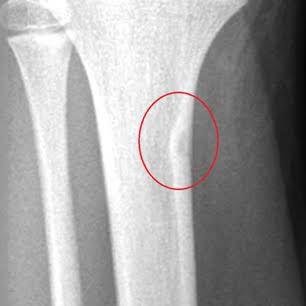

An osteoid osteoma is a noncancerous (benign) bone tumor. Each tumor usually measures less than 1 inch across. These tumors don’t grow or spread anywhere else in your body. Osteoid osteomas most often develop in the long bones of your body. These long bones include your shin (tibia) and thigh (femur) bones. Osteoid osteomas may also form in your: Arms. Hands or fingers. Feet or ankles. Spine. This condition usually causes aching, dull pain that worsens at night. Healthcare providers treat osteoid osteomas with non-steroidal inflammatory drugs (NSAIDs) or surgery.